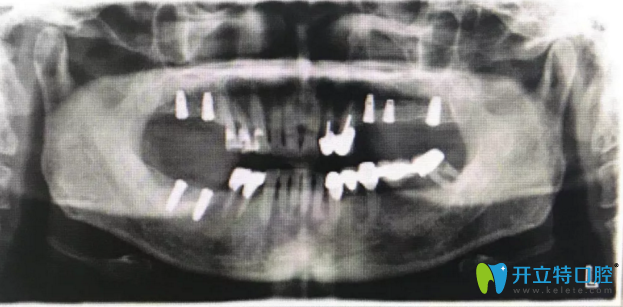

種植后全景片

修復(fù)完成后拍片

種植修復(fù)作為牙缺失修復(fù)的選擇,患者戴牙后和活動(dòng)修復(fù)有明顯的區(qū)別,舒適度和咀嚼效果媲美真牙,所以患者反響很好,并決定把左下烤瓷橋拿掉后也種植修復(fù)。